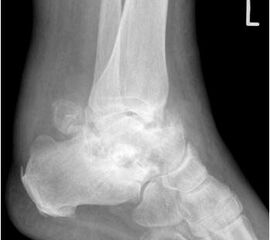

• Primäre oder posttraumatische Arthrose des OSG und USG (Abbildung 1, Abbildung 2).

• Pseudarthrosen (Abbildung 5, Abbildung 6).